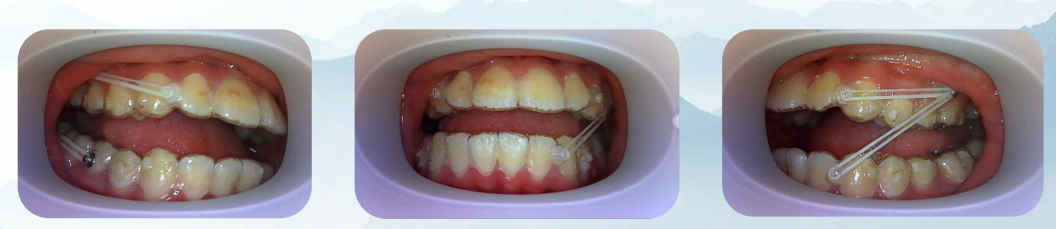

4.数字化复诊监控。科室为无法及时复诊的隐形患者提供远程复诊服务,可以减少患者的复诊次数,提供方便。

(口内照片为患者利用远程拍照工具自行拍摄,便于医生监控)